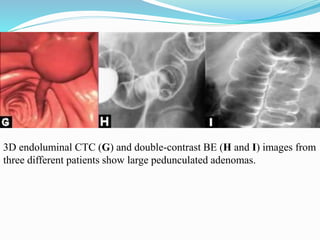

This document discusses colorectal polyps. It defines polyps and describes their types, including neoplastic and non-neoplastic polyps. It discusses adenomatous polyps in depth, noting their malignant potential increases with size over 1cm and villous architecture. Radiological diagnostic methods for polyps including single and double contrast barium enema and CT colonography are explained. The document provides an overview of polyp pathogenesis and genetic syndromes like FAP that increase cancer risk.